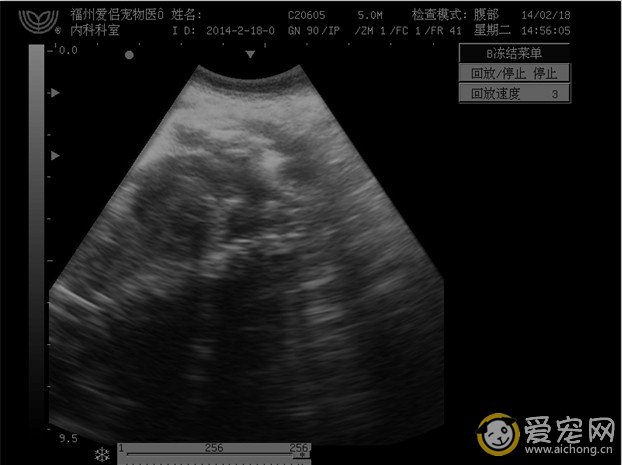

以下是一个难产的小鹿狗串,难产的原因是胎儿过大,而且第一次进入产道的胎儿胎位不正,看以下的图就知道怎么回事了。B超诊断能看到4个胎儿,但只有2个胎儿有心跳,其他第一第二进入产道的胎儿都确认死胎,没有心跳。